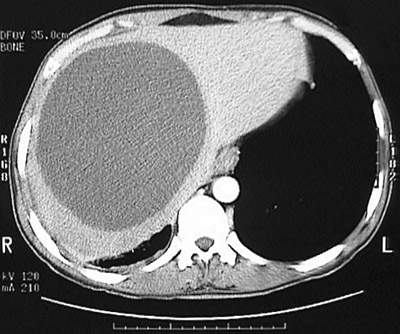

The

large unilocular cyst

seen here in this abdominal CT scan is occupying a large part of the liver. This appearance is consistent with a hydatid cyst of

Echinococcus granulosus

.